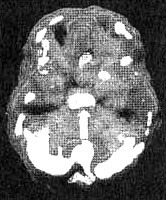

Иллюстрация к книге — Измените свой мозг - изменится и жизнь! [i_031.jpg]

Трехмерное изображение снизу — активный мозг